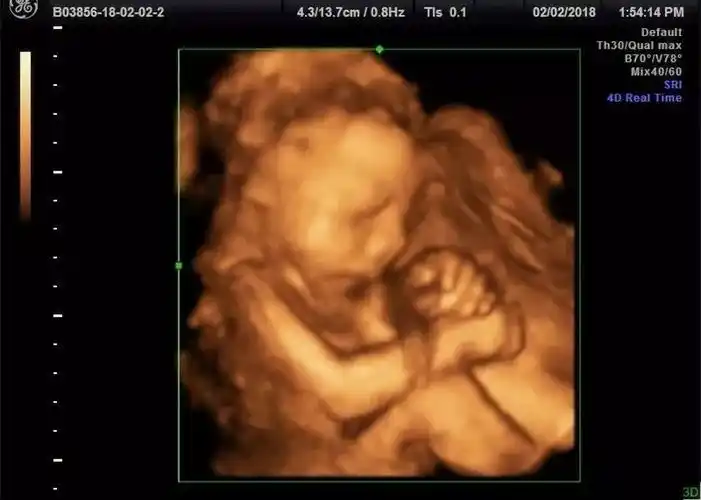

照四维的时候拍的,有没有会看男孩女孩的?第一胎,超好奇

怀七个月做的四维,哈哈,宝妈们看看这是男孩女孩

今天做的四维,图三是孕早期拍的b超,男孩女孩我都喜欢,纯属好奇想知道

宝妈们来看看我的四维~是男宝女宝